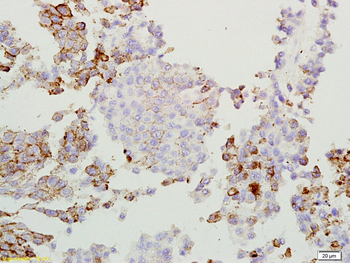

应用稀释比例:WB=1:500-2000, IHC-P=1:100-500, IHC-F=1:100-500, IF=1:100-500

IF, IHC-Fr, IHC-P, WB